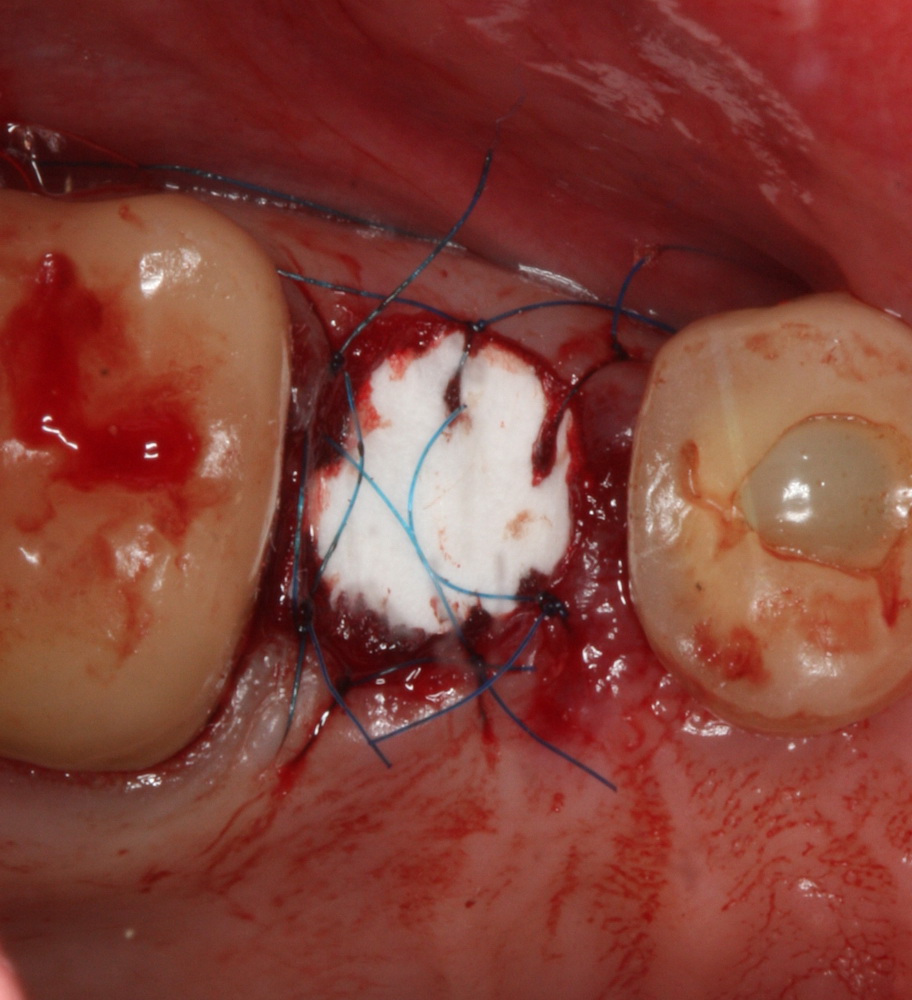

Затем к краям лунки подшивается Mucograft Seal:

Это относительно новый форм-фактор Geistlich Mucograft, специально предназначенный для таких случаев:

Которую мы удаляем, а саму лунку консервируем точно по такому же принципу, что и лунку #47 (Neocones, Bioss Collagen):

И «запечатываем» с помощью Mucograft Seal:

Очень аккуратно удалили зуб. Убрали из лунки все грануляции. В область верхушки корня зуба — Neocones, остальная часть альвеолы — Bioss Collagen. Сама лунка запечатывается Mucograft Seal:

Который подшивается к ее краям: